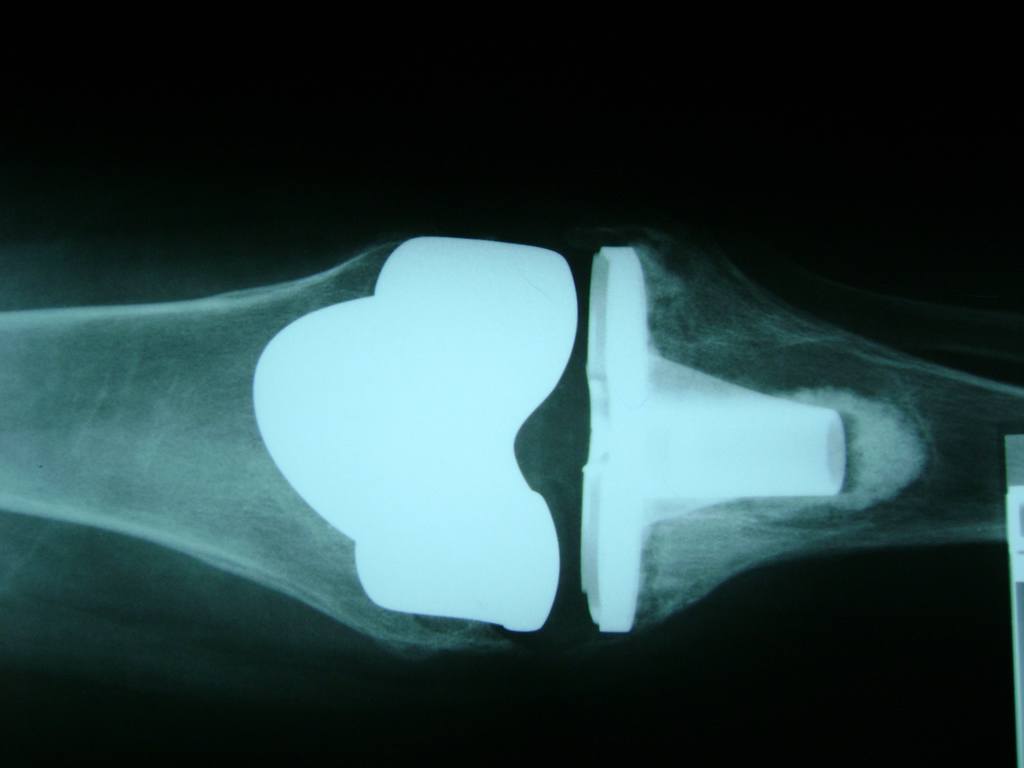

Cirugía de Rodillas